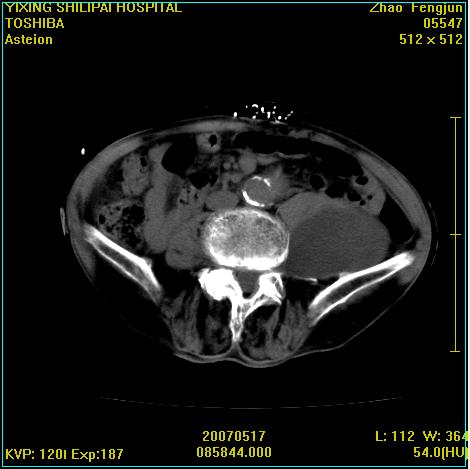

考虑:1、左侧腰大肌囊实性占位性病变(囊性神经根鞘瘤?);

2、右侧兰尾区囊性占位性病变(兰尾囊肿?囊腺癌?类癌?)

以下是引用xiaoniu在2007-5-26 10:45:00的发言:[br]腰大肌的病变应该没有问题,增强扫描还有轻度强化及细小血管影入内,应该排除脓肿,考虑占位性病变,腰大肌的占位多考虑:神经源性肿瘤。另外腹主动脉下端有真假腔的强化,考虑:主动脉夹层。[br][br][本贴已被 xiaoniu 于 2007-5-26 10:46:39 修改过]

以下是引用老爱克斯新网客在2007-5-26 18:26:00的发言:[br]1左下腹囊实性占位肿块,增强后不均匀强化,位于脊柱旁,椎体骨质无破坏软组织无肿胀,考虑神经源肿瘤神经鞘瘤可能大,2右下腹囊性占位性病变,增强后囊壁强化,考虑阑尾囊肿或囊腺瘤,